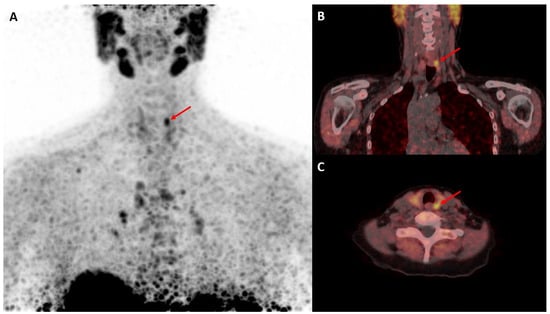

- Seyedinia, S.S.; Mirshahvalad, S.A.; Schweighofer-Zwink, G.; Hehenwarter, L.; Rendl, G.; Pirich, C.; Beheshti, M. Evolving Role of [18F]Flurocholine PET/CT in Assessing Primary Hyperparathyroidism: Can It Be Considered the First-Line Functional Imaging Approach? J. Clin. Med. 2023, 12, 812. [Google Scholar] [CrossRef]